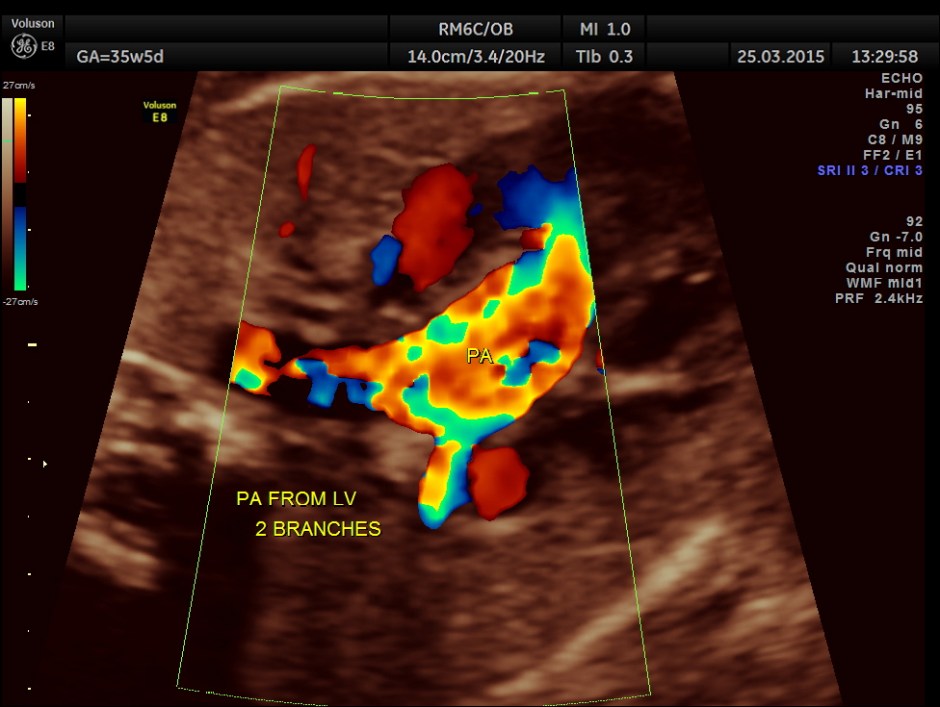

The artery coming out of left ventricle branches into two – suggestive of pulmonary artery.

The great artery arising from the LV branches into two suggestive of pulmonary artery.